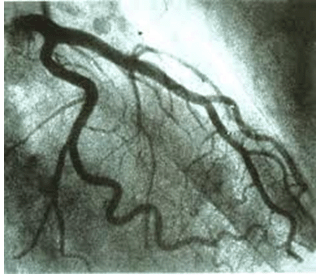

正常左冠状动脉造影图